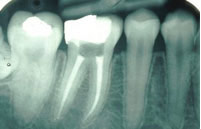

Root Canal Treatment

The removal of the infected or irritated nerve tissue that lies within the root of the tooth. It is this infected pulp tissue that causes an eventual abscess.

The length of the root canal is determined and the infected pulp is removed. At the same visit, the canal where the nerve is located will be reshaped and prepared to accept a special root canal filling material. The number of visits necessary to complete your root canal will depend upon several factors including the number of nerves in the tooth, the infected state of the nerve, and the complexity of the procedure.

The final step in your root canal will be the sealing of the root canal with a sterile, plastic material called gutta percha. This is done in order to prevent possible future infection. If treated early, root canal therapy need not be uncomfortable. With the use of local anesthetics, the entire procedure can be totally painless.

The tooth will then possibly need a post and core and a crown in order to re-establish normal form and function. This decision will be based upon several additional factors.